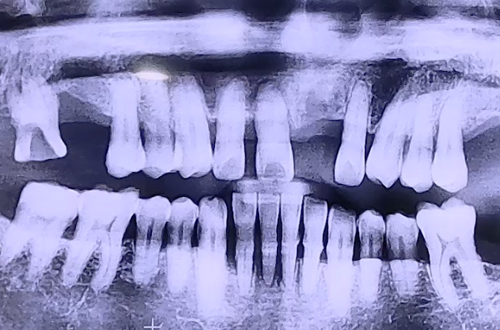

AFTER

불편함을 말씀하셨기 때문에 임플란트가 단단히 굳는 기간 동안 불편하시지 않도록

임시 치아를 예쁘게 제작하여 수술 당일 바로 끼울 수 있도록 도와드렸습니다.

그 후 보철이 완성되어 예쁘고 튼튼한 앞니로 치료해 드렸고,

이후로도 지속적인 검진을 통해 문제 생기는 부분 없는지 체크해드릴 예정입니다.

환자분께서 매우 만족해하셔서 저희도 기쁜 치료였답니다! ^^